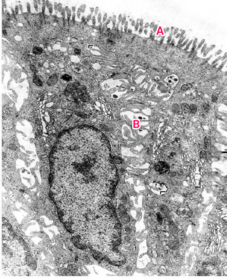

Parietal cell TEM "NOTICE apical occluding junction"

A : Lumen B : Microvilli C : Intracellular canaliculas D : Mitochondria